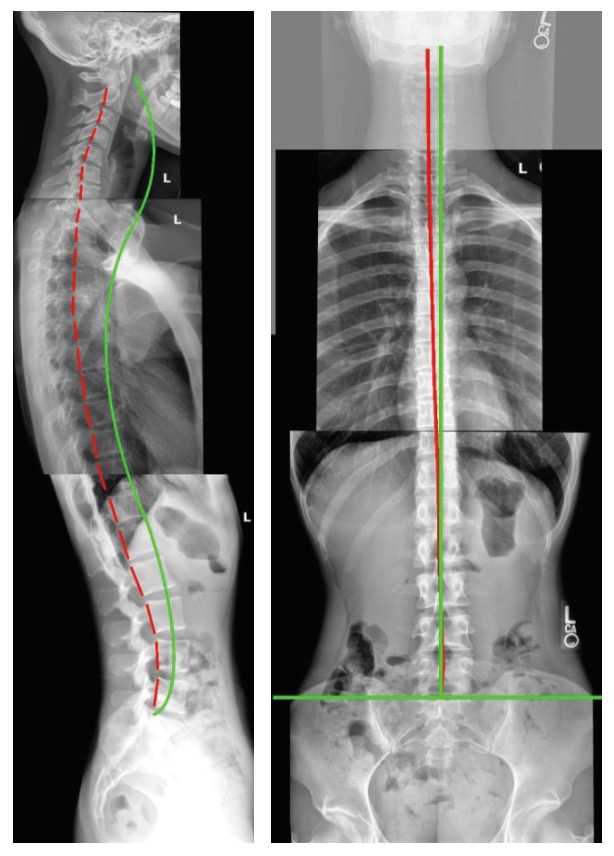

レントゲン診断で痛みの原因を見極め、姿勢改善、背骨矯正によって根本治 療が可能。ストレートネックや側弯症に有効なCBP®治療を行っている。